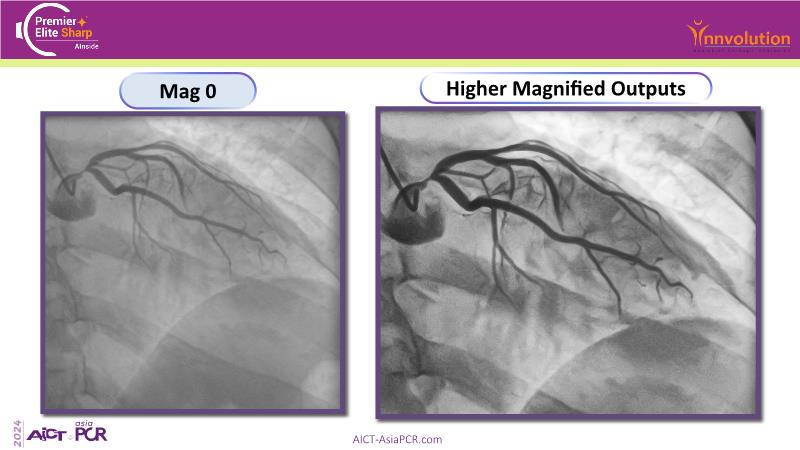

Exploring a recorded case of image-guided PCI of distal left main disease, as well as a new paradigm in AI-driven imaging, and learn how coronary imaging aids in decision-making, optimises final outcomes, and enhances stent clarity to guide results in complex PCI procedures. Watch now to deepen your knowledge of advanced imaging techniques for better procedural success.

- To discover how coronary imaging can help in deciding on a strategy in complex distal left main disease